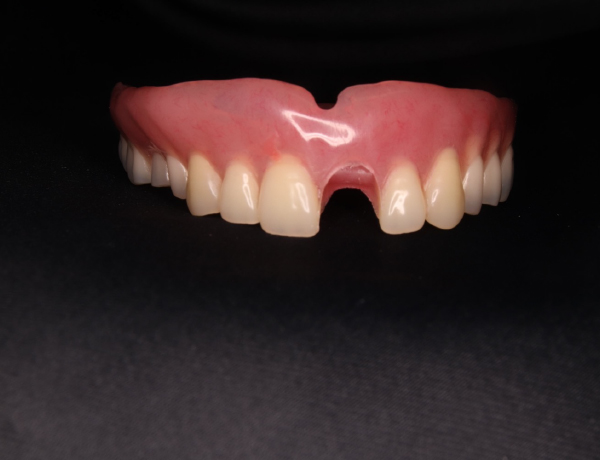

保険外(自費)入れ歯完成

上あご

患者さんのかみ合わせやかむ力を考慮して、金属の入れ歯を選択しました。写真を見ると分かると思いますが、入れ歯の金属の部分がとにかく大きく広くとってあります。この金属の設計は、先代の田中久敏に習ったデザインになりますが、口蓋の吸収しない部分は、金属で出来るだけ広く覆って、それ以外の部分は、ピンクのレジンで覆っています。

このように金属の部分を大きくすると強度が増しますので、割れたりヒビが入ったりする可能性が少なくなります。